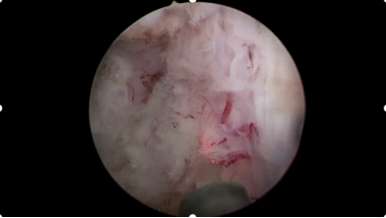

它是一種專注于改善前列腺增生所致排尿問題的微創(chuàng)治療方式,整個過程類似一次“精準(zhǔn)的蒸汽理療”——醫(yī)生借助一根纖細(xì)柔軟的治療探針,經(jīng)人體自然通道抵達(dá)前列腺位置,向增生組織釋放高溫水蒸氣,水蒸氣在目標(biāo)區(qū)域內(nèi)快速釋放能量,使部分增生組織發(fā)生改變,隨后,這些組織會隨著時間被人體自然吸收、逐步萎縮,從而減輕其對尿道的壓迫,達(dá)到拓寬通道、改善排尿感受的目的。